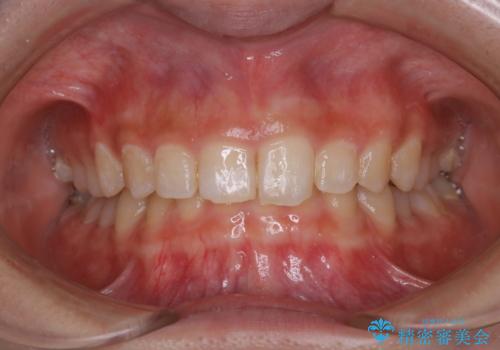

歯の染め出しとPMTCで口腔内ケア

- しばらく歯科でのメンテナンスを受けていないため、歯磨きのチェックとクリーニング希望とのことで来院されました。

染め出しをしてのブラッシング指導とPMTCを行いました。